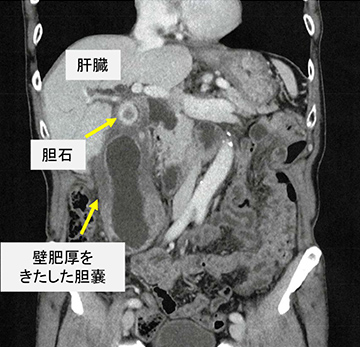

急性胆嚢炎

おもに胆石が原因で胆嚢に急性の炎症が起こった状態です。 急激な炎症により発症し、強い症状(腹痛・発熱・嘔気・嘔吐など)を伴います。 また、何らかの重症疾患により食事を摂取していない患者さんでは胆石が無くても胆嚢の動きが悪いために急性胆嚢炎を起こすことがあります。

慢性胆嚢炎

軽症から重症までさまざまな急性胆嚢炎を繰り返した後に、炎症性変化により胆嚢の壁が厚く硬くなった状態で、胆嚢の拡張・収縮機能の低下を来します。

慢性胆嚢炎は胆嚢癌との鑑別が重要です。

一般的に慢性胆嚢炎と胆嚢癌の鑑別はエコー検査やCT検査を用いて行われますが、胆嚢癌ではないことを十分に確認できない場合には手術により切除した実物によって判断する必要があります。

また、慢性胆嚢炎を長期間放置すると、周囲の臓器(胃・十二指腸・大腸など)との癒着のために大がかりな手術を要することがあります。